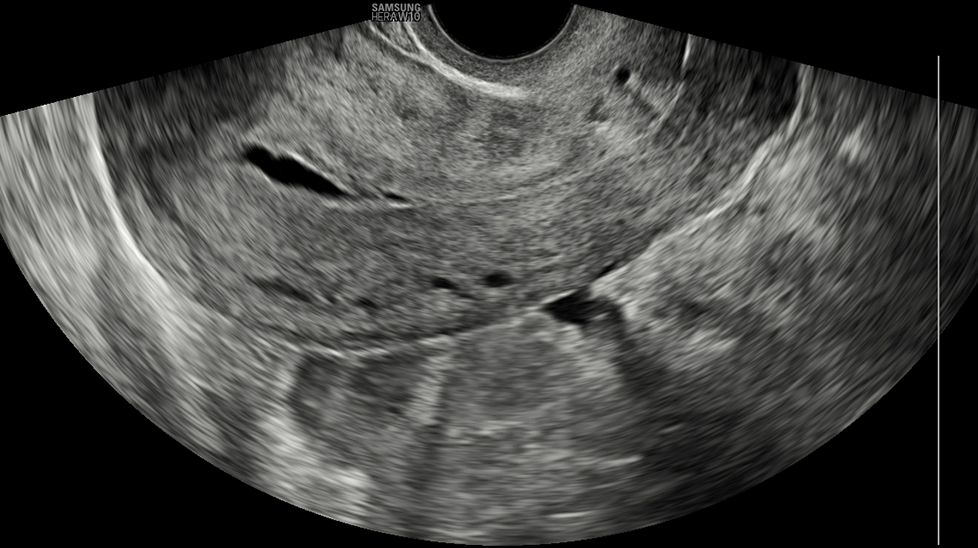

Контур матки Контур матки автоматически выделяет центральную линию и толщину изогнутого эндометрия и обеспечивает вид короны в 3D, выровненный по центральной линии. Кроме того, информация о классификации пороков развития матки приводится в соответствии с выбранными рекомендациями ESHRE / ESGE* или ASRM*.